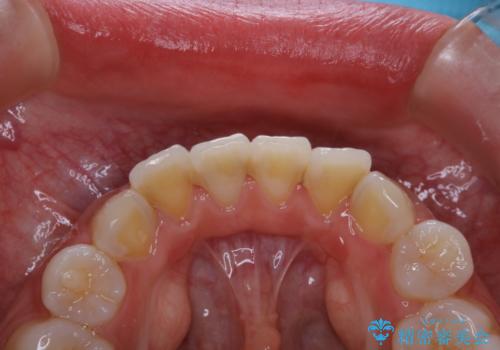

- 子供の頃以来のかなり久しぶりの歯科医院への来院とのことで、プラーク・歯石がべっとり付着していました。

古くからの磨き残しや、歯石などにより、歯肉に炎症がみられ、かなり汚れが多く付着していました。PMTC60分コースで徹底的に汚れをおとしました。施術後の歯肉に出血が見られますが、次第におさまります。